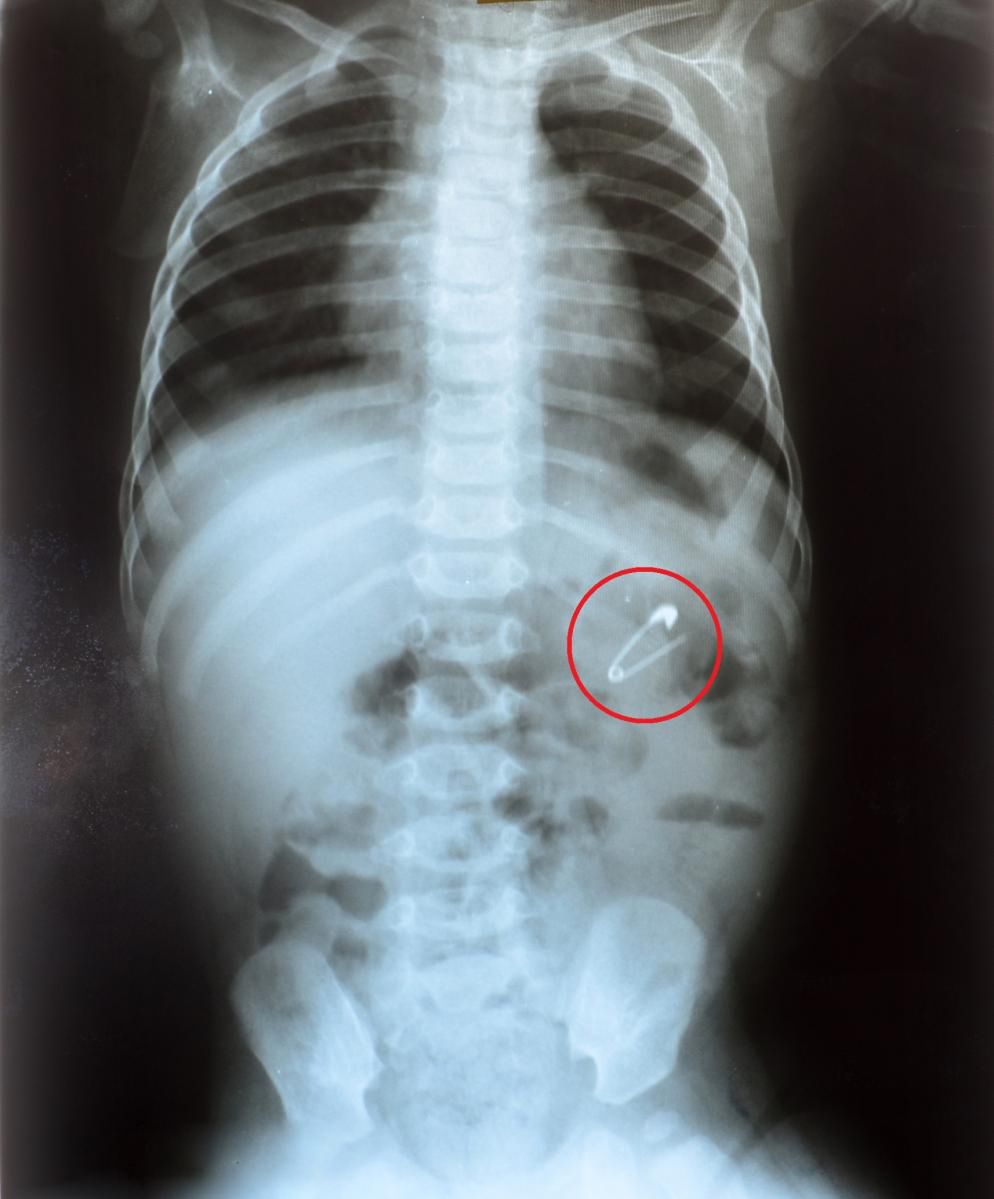

- Wodne koraliki (water beads, aqua beads) nie zawsze są widoczne na zdjęciu rentgenowskim lub tomografii komputerowej. To bardzo utrudnia określenie, w którym miejscu układu pokarmowego się znajdują – mówi Nikki. – Można je jednak wykryć za pomocą ultradźwięków, ale trzeba mieć świadomość, że niektóre z nich mogą zostać pominięte – dodaje.